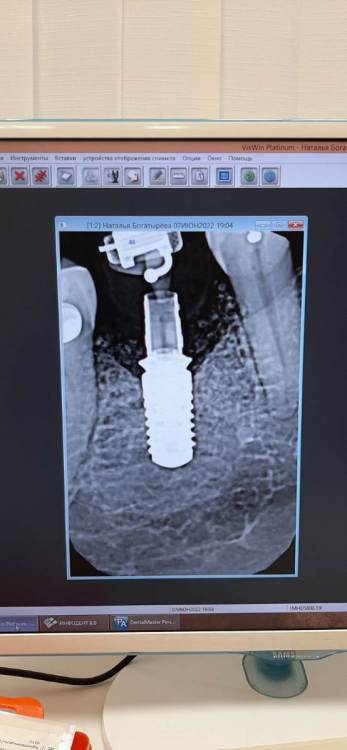

Здравствуйте, возможен ли выход костного материала наружу  через 1 год и 3 месяца после имплантации? Если возможен, то в чем причина? И второй вопрос  - где должна быть коронка, где красные линии, или где желтые, и что это на снимке - отмечено зеленым?

Возможен

Оба варианта возможны, все зависит от толщины тканей.

Зеленым Вы отметили на снимке заглушку (обычно - тефлоновую) шахты абатмента, она нужна чтобы внутрь ничего не попадало.